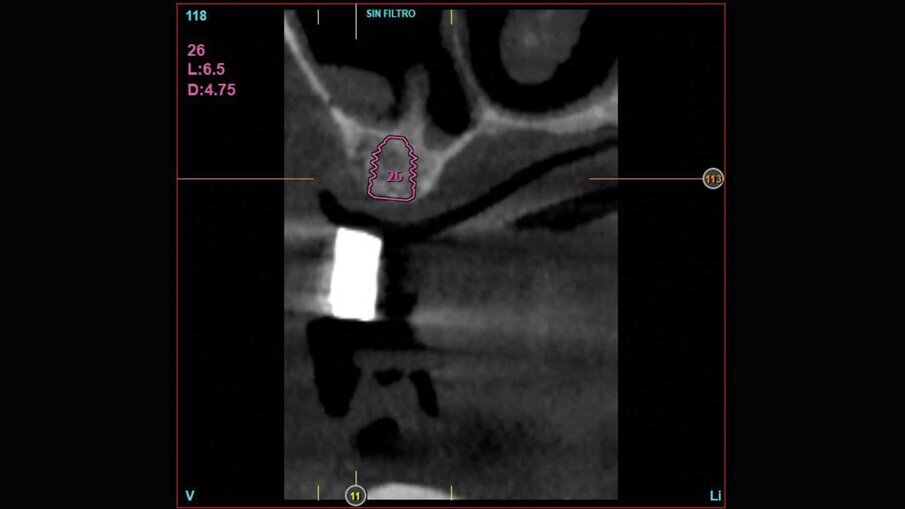

Al paziente fu spiegato che la strategia migliore consisteva nell’estrazione di tutti gli elementi dentari e l’inserimento di sei impianti in ogni arcata dentaria e successivamente il ripristino delle arcate con due protesi tipo Toronto. Si decise di non estrarre subito i quattro canini perché sarebbero serviti per stabilizzare le mascherine chirurgiche durante la chirurgia. Lo studio del caso e la sua realizzazione fu fatta con metodo analogico. Due modelli in gesso furono montati alla giusta dimensione verticale e fu realizzato il montaggio dei denti per visualizzare il risultato finale (Fig. 3). Dal montaggio dei denti furono realizzate le mascherine chirurgiche che sarebbero state utilizzate per gli esami radiografici tridimensionali e avrebbero guidato il posizionamento degli impianti durante la chirurgia. All’esame radiografico tridimensionale (Figg. 4-7) si notava la presenza di una quantità esigua di osso coronalmente ai seni mascellari e al nervo alveolare inferiore. Si decise di inserire impianti extracorti 4,5 mm di lunghezza in queste zone, per evitare sia impianti inclinati sia cantilever molto estesi. Lo studio della scala dei grigi, o scala Hounsfield, mostrava una densità ossea tale da consentire il carico immediato anche in queste zone. Ovviamente sarebbe stata necessaria la conferma intra-operatoria valutando clinicamente la compattezza dell’osso tramite la fresatura.

La fase chirurgica fu eseguita circa due mesi dopo le estrazioni. Al paziente fu somministrata terapia antibiotica preventiva dalla mattina dell’intervento chirurgico e protratta per sei giorni. Fu somministrata anestesia locale con Articaina 1:100000 e adrenalina al 2%. Furono scollati lembi a tutto spessore e furono inseriti sei impianti BTI Core in ogni mascellare. Fu eseguito prima l’intervento sul superiore e dopo un mese sull’inferiore su richiesta del paziente che aveva paura di postumi eccessivi. Gli impianti furono posizionati con l’ausilio delle mascherine chirurgiche (Figg. 8, 9) che furono usate per la registrazione della posizione degli impianti secondo la metodica del modello modificato descritta dal dott. Lionello Biscaro. La posizione risultava molto accurata grazie alla stabilizzazione offerta dai canini residui che furono estratti subito dopo l’inserzione degli impianti per consentire la registrazione della posizione relativa degli impianti (Figg. 10, 11). In particolare nella posizione del dente 16 fu inserito un impianto BTI Universal-Plus 5 mm di diametro

x 4,5 di lunghezza, in posizione 26 un impianto BTI Core 3,75 x 6,5 mentre in posizione 36 e 46 furono inseriti due impianti BTI Core 4,75 x 4,5. La superficie UnicCa degli impianti fu bagnata con frazione F2 ottenuta dal plasma per centrifugazione del sangue del paziente. Furono avvitati i pilastri Multi-Im e furono fatte le registrazioni necessarie a comunicare al tecnico la posizione degli impianti rispetto ai modelli già montati e la posizione reciproca degli impianti, secondo la tecnica del modello modificato citata precedentemente. I pilastri di guarigione furono avvitati, le suture applicate e il paziente fu dismesso.